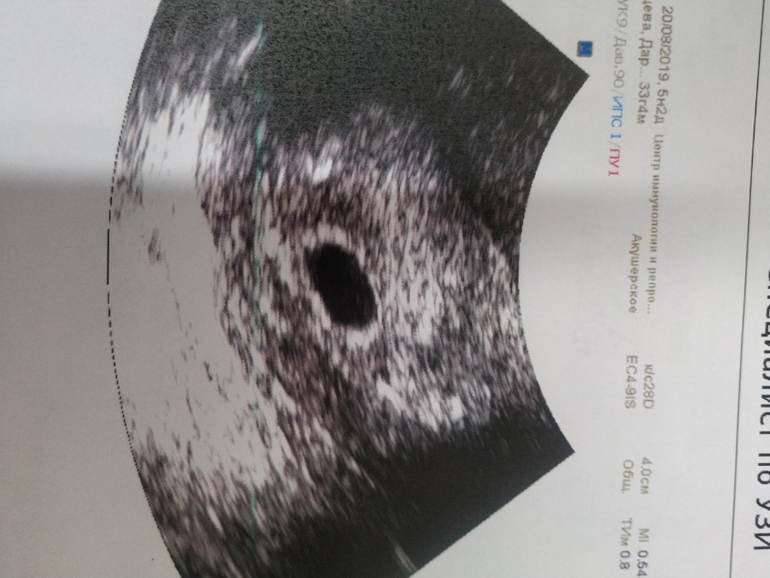

Девочки,подскажите,может ли быть все хорошо? Пошла на узи,врач назначила для подтверждения маточной беременности. Хгч сдаю регулярно,рост нормальный. Сегодня 23 ДПО или 10дз. Это моя первая в жизни и очень долгожданная беременность,очень переживаю. НА узи нашли только плодное яйцо д9мм,про жм и тем более эмбрион ничего не сказали,врач какой-то вялый,я спрашиваю все хорошо,он ну поменьше ,типо маленький срок. спросил про хгч,сказал, ну это нормальный рост. Типо развивающуюся пока поставить не могу,просто беременность малого срока. Приходи мол через 2 недели.(оборудование должно быть хорошее,делала в ЦИРе)

Не было ничего на 5 неделе, фото скинула вам. Только плодное яйцо. Срок маленький ещё не видно ничего. Не надо переживать, это вредно

Это узи на 5 неделе, а следующее уже в 7 недель.